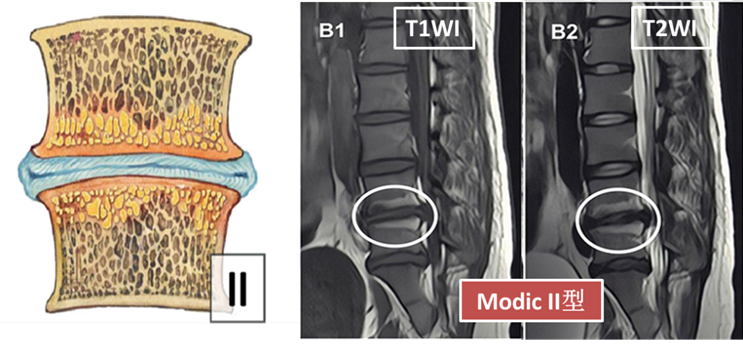

Modic Ⅱ 型(脂肪浸润期):表现为T1WI高、T2WI高、T2WI压脂等低信号;对应病理学表现:脂肪浸润骨髓,黄骨髓成分增多,终板区破裂处炎性反应。